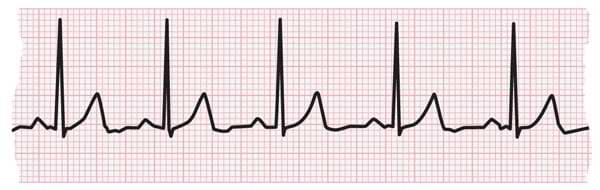

An electrocardiogram measures the electrical activity of the heartbeat. With each beat, an electrical wave travels through the heart. This wave causes the muscle to squeeze and pump blood from the heart. A normal heartbeat on an EKG will show the rate and rhythm of the contractions in the upper and lower chambers.

EKG strip showing a normal heartbeat